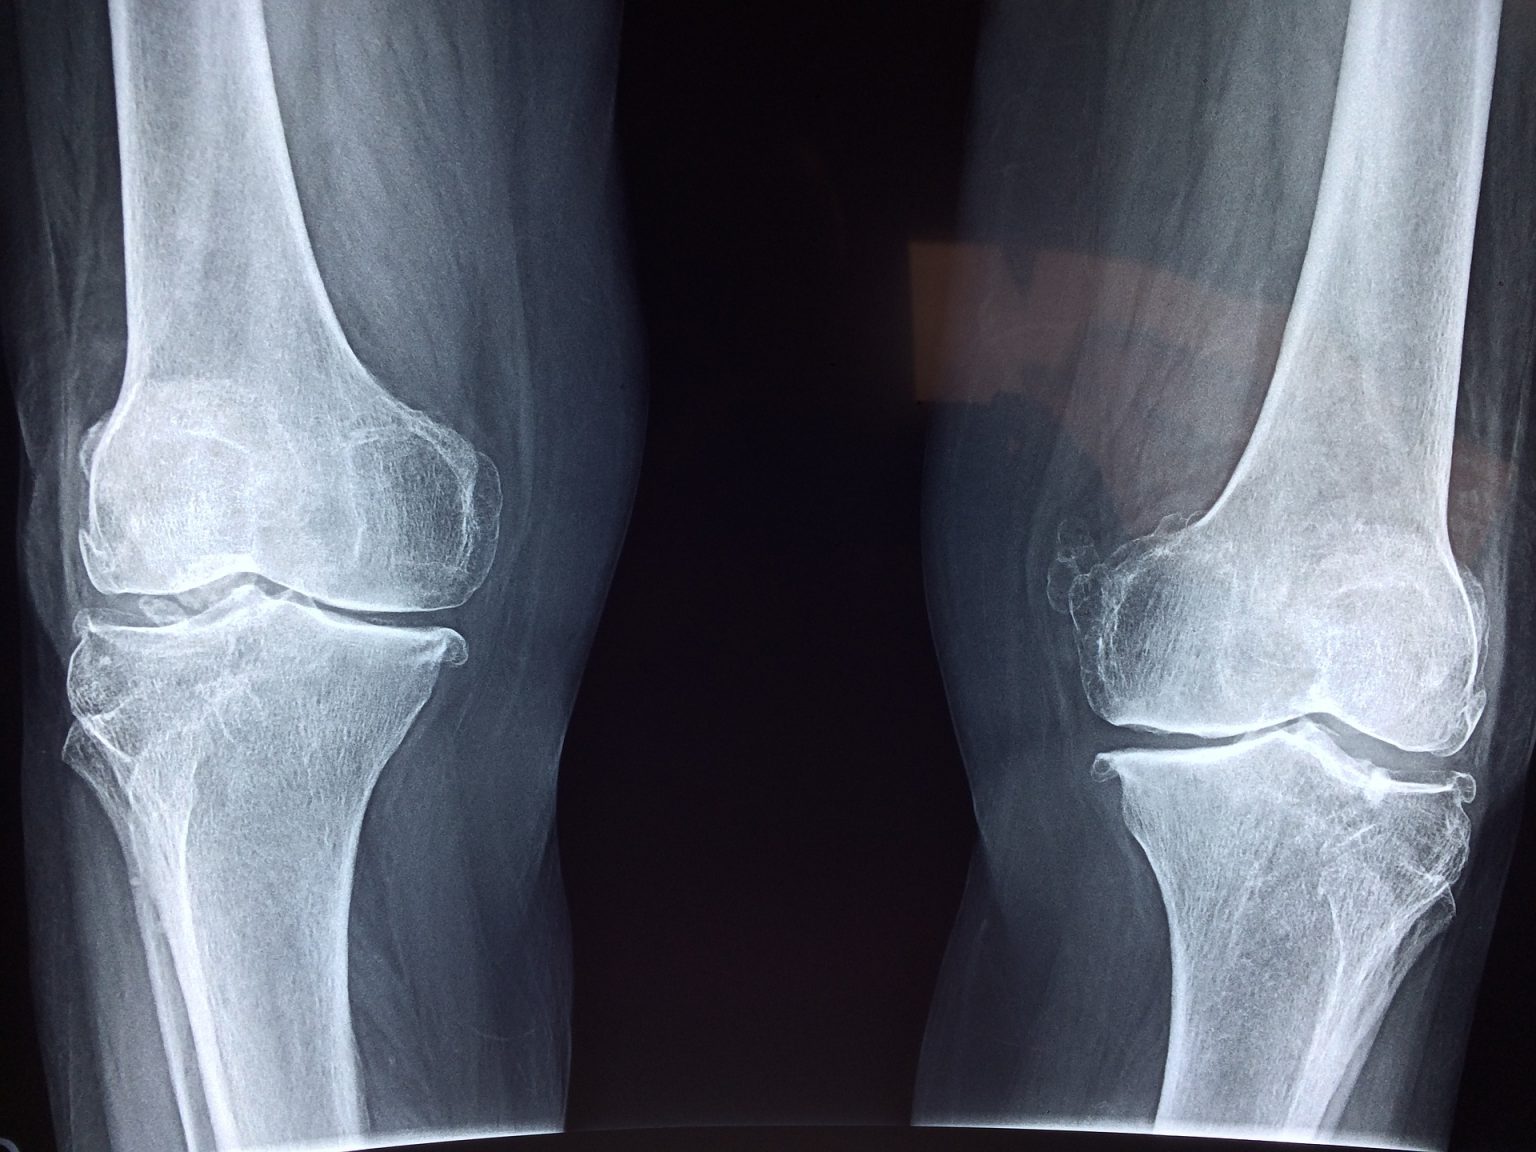

From www.health.harvard.edu

When is it time for a knee replacement? Harvard Health How Much Are Knee Worth When surgery is required for a torn anterior cruciate ligament. As to knee injuries, you’ll likely see a settlement amount above the average when surgery is required to repair the injury. Then read examples of recent knee injury verdicts and. The average workers' comp knee injury settlement is $35,332, though how much you get depends on the severity of your. How Much Are Knee Worth.

From www.parcofontario.com

Partial vs Total Knee Replacement Which is the Better Option? The How Much Are Knee Worth Learn what factors determine the value of your knee injury insurance claim or lawsuit. Severe knee and leg injuries typically require surgery, intense therapy, and a long recovery. The average workers' comp knee injury settlement is $35,332, though how much you get depends on the severity of your injury. In an ideal world, the answer would be yes, but unfortunately,. How Much Are Knee Worth.